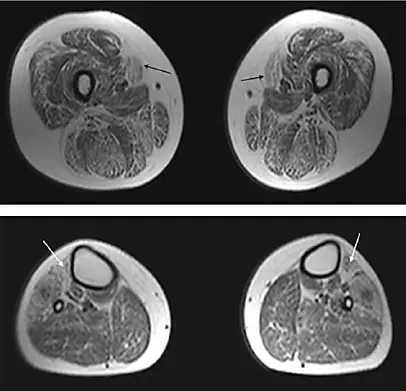

Imagen de miopatía nemalínica

Urgencias pediátricas ante la miopatía nemalínica: desafíos y estrategias del cuidado enfermero

Este artículo aborda los retos de la atención urgente a niños con miopatía nemalínica, una enfermedad rara de alta complejidad. Se destaca el papel crucial de la enfermera de urgencias en la estabilización clínica, el apoyo emocional y la educación a las familias. La falta de formación específica y de protocolos dificulta la práctica asistencial, lo que refuerza la necesidad de impulsar la formación, la coordinación interprofesional y la continuidad de cuidados para mejorar la calidad de vida de los pacientes y sus cuidadores.